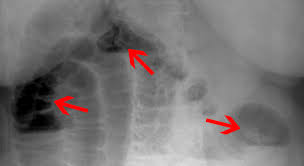

Invagination Schmerzhafte Darmeinstulpung Bei Kleinen Kindern

Invagination Schmerzhafte Darmeinstulpung Bei Kleinen Kindern from www.praxisvita.de